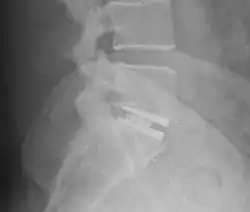

X-ray of interbody fusion cage in L5S1 vertebrae.

An interbody fusion cage (colloquially known as a "spine cage") is a prosthesis used in spinal fusion procedures to maintain foraminal height and decompression. They are cylindrical or square-shaped devices, and usually threaded. There are several varieties: the Harms cage, Ray cage, Pyramesh cage, InterFix cage, and lordotic LT cage, all of which are made from titanium; the Brantigan cage, made from carbon fibre; and the Cortical Bone Dowel, which is cut from allograft femur. The cages can be packed with autologous bone material in order to promote arthrodesis.[1] Such implants are inserted when the space between the spinal discs is distracted, such that the implant, when threaded, is compressed like a screw. Unthreaded implants, such as the Harms and Pyramesh cages have teeth along both surfaces that bite into the end plates.[1]

Once placed, the cages resist flexion and extension of the spine, and axial forces across the ventral and middle columns.[1]